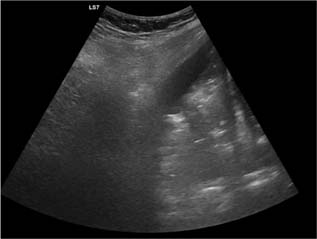

Pleural line (Figure 3): in a normal lung, only the pleural line can be seen. This appears as a hyperechoic and sliding line, moving forward and backward with ventilation. This is the result of the movement of the visceral pleura against the parietal pleura during the respiratory cycle.

A-lines (Figure 4): these appear as motionless and regularly spaced horizontal lines under the pleural line. These correspond to normal reverberation artefact of the pleural line. A-lines and lung sliding define normal aeration.62